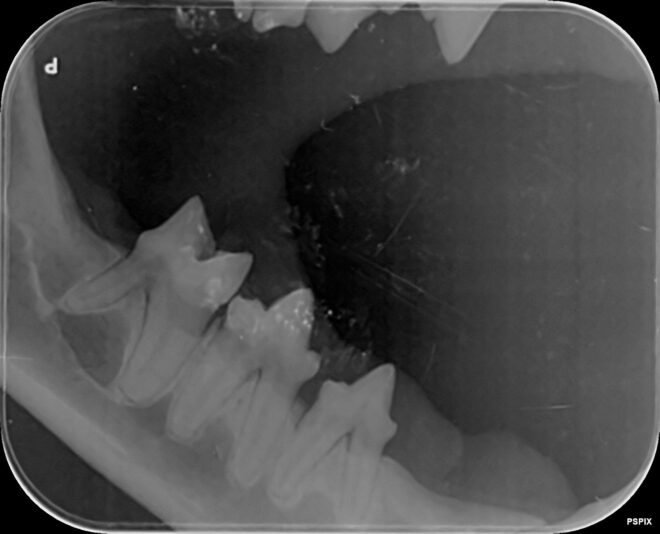

case gegeneraliseerde ontsteking peridontale ruimte

We hebben deze dentale RXen genomen van een jonge oosterse korthaar met chronische gingivitis sinds de geboorte. Op deze Rxen zie ik een verbreed paradontium en een te witte ‘lijn’ bij de aflijning van het alveolair bot. Is er een aandoening die beschreven is bij onze katten en past bij dit beeld? Hoe gaan we verder te werk? Meloxicam lijkt…